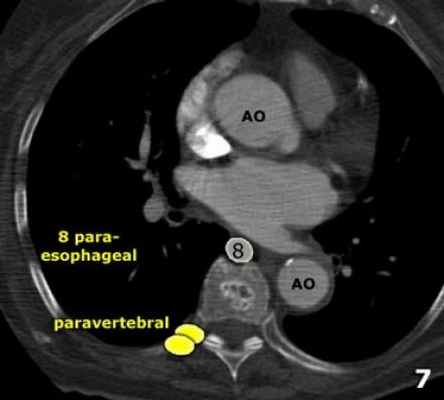

Нижние медиастинальные лимфатические узлы 7-9

7. Подкаринальные лимфатические узлы.

8. Параэзофагеальные лимфатические узлы. Лимфатические узлы ниже уровня карины.

9. Узлы легочной связки. Лежат в пределах легочной связки.

7. Подкаринальные лимфатические узлы

Эти лимфатические узлы расположены ниже уровня бифуркации трахеи (карины), но не относятся к нижнедолевым бронху и артерии. Справа они располагаются каудальнее нижней стенки промежуточного бронха. Слева они располагаются каудальнее верхней стенки нижнедолевого бронха.

Слева лимфатический узел 7 группы справа от пищевода.

8. Параэзофагеальные лимфатические узлы

Эти лимфатические узлы ниже подкаринальных лимфатических узлов и распространяются каудальнее до диафрагмы.

На изображении слева ниже уровня карины справа от пищевода обозначен лимфатический узел 8 группы.